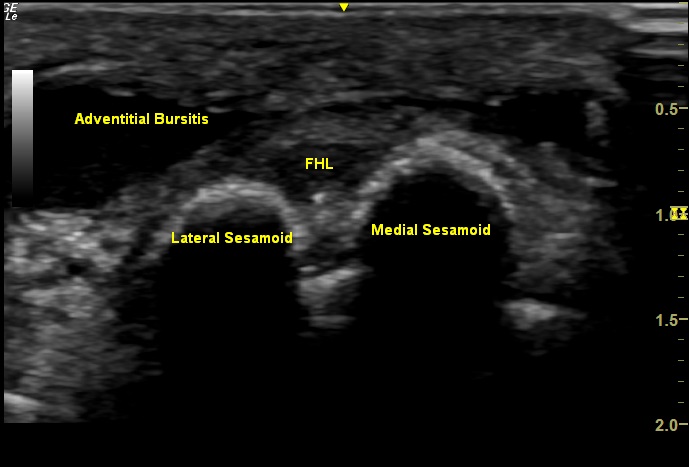

Labeled Short Axis view of the medial plantar forefoot, demonstrating adventitial bursitis overlying the medial and lateral sesamoids with the flexor hallucis longus (FHL) tendon visualized between the sesamoids.